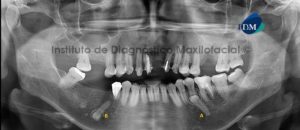

Paciente femenina de 51 años de edad que es referida para el estudio imagenológico previo a la colocación de implantes dentales. A la evaluación de